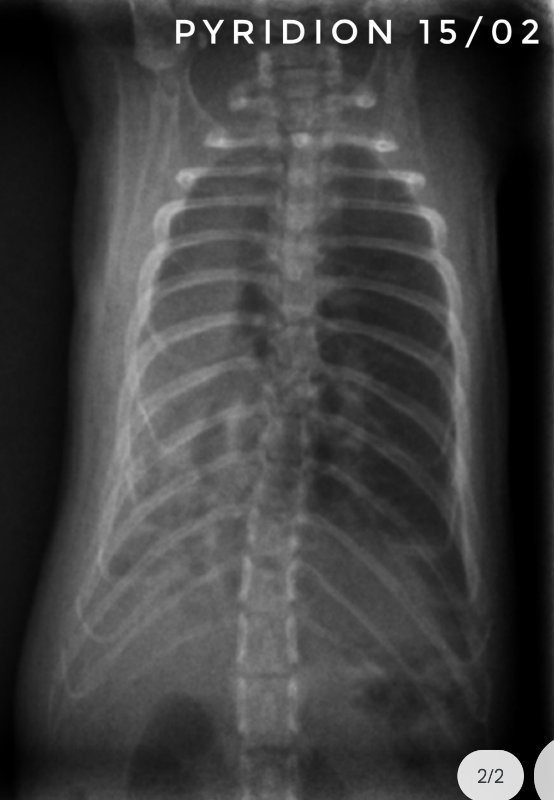

Toujours pour ceux que ça intéresse, les dernières  radios et le suivi du poids (Pyridion a commencé à perdre du poids le 04 mars, traitement changé le 08)

Il nous reste donc 3 malades : Drupe, Caryopse et Pyridion.

Pyridion a eu un vrai mieux la semaine dernière et grosse dégradation là. Les radios n'ont pas bougé depuis 3 semaines...